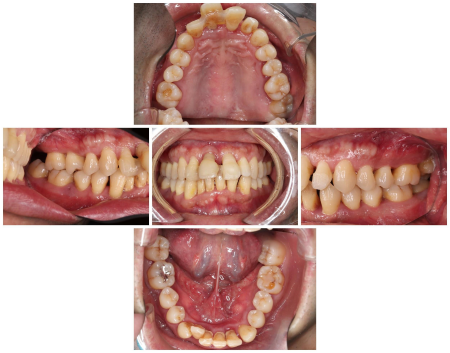

症例(歯周病治療)

40代男性 重度の「若年性歯周病」を改善させ、自然な見た目の「ジルコニアブリッジ」で美しい口元にした症例

治療前

治療後

診療種別 自由診療

治療期間・回数の目安 3年

治療費総額の目安 776,600円

主なリスク ブリッジは土台となる歯に負担がかかるため、将来的に歯が揺れたり、歯の根が割れたりする可能性があります/噛み合わせや歯ぎしりが強い場合、被せ物が破損する可能性があります/治療が終わった後も、十分なセルフケアが必要です/正しいブラッシングやメンテナンスを行わない場合、歯石の付着や虫歯が生じる可能性があります